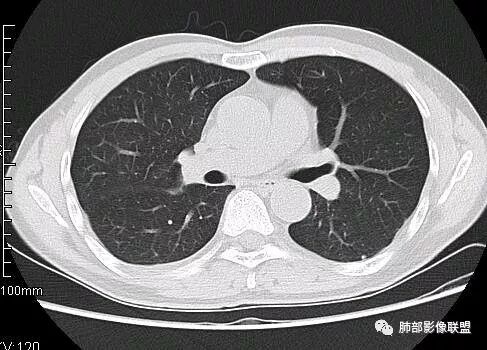

南边:病灶边界清,提示侵袭性弱,膨胀生长为主;这时候我们提示病灶不应该是支气管关系密切,提示间叶来源或胸膜来源

南边:结果:肉瘤

3.肿块常常较大,甚至巨大,病灶边界一般清楚,影像上常有假包膜样结构、有膨胀性生长的特点,影像科医师有时甚至会纠结其来源于肺部或是胸壁纵隔。常见的肺癌肿块,很少有机会能长成这样的规模。

4.边缘可以有浅切迹,部分病灶会有铸型样外观,但大体十分圆钝,不会出现典型的分叶和毛刺,也很少会出现胸膜牵拉。支气管常推移,有明显的支气管阻塞时也较少观察到相关的阻塞性炎症。

5.病灶密度大多不均,不规则坏死液化,少数病例出现钙化。增强扫描常观察到由外而内的厚壁不均匀强化,中央半岛样强化等等,厚壁中或实性区常能显示血管影。一些病灶中央呈现边界清楚囊样变。

3.PPS在肺实质内成膨胀性生长,很少侵犯或突破支气管黏膜,影像学表现密度均匀、边缘光整的肿块,少有空洞、分叶、毛刺、钙化,一般为单发,体积较大,直径多在4cm以上,增强后呈不均匀强化。